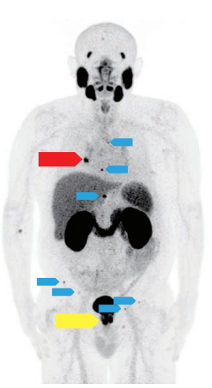

PET-CTは詳細な機能情報と形態情報を同時に得ることができ、より小さい病変を正確に検出できます。 検査は、腫瘍の存在・拡がりや転移の確認のみにとどまらず、治療効果判定、治療計画への応用が求められています。